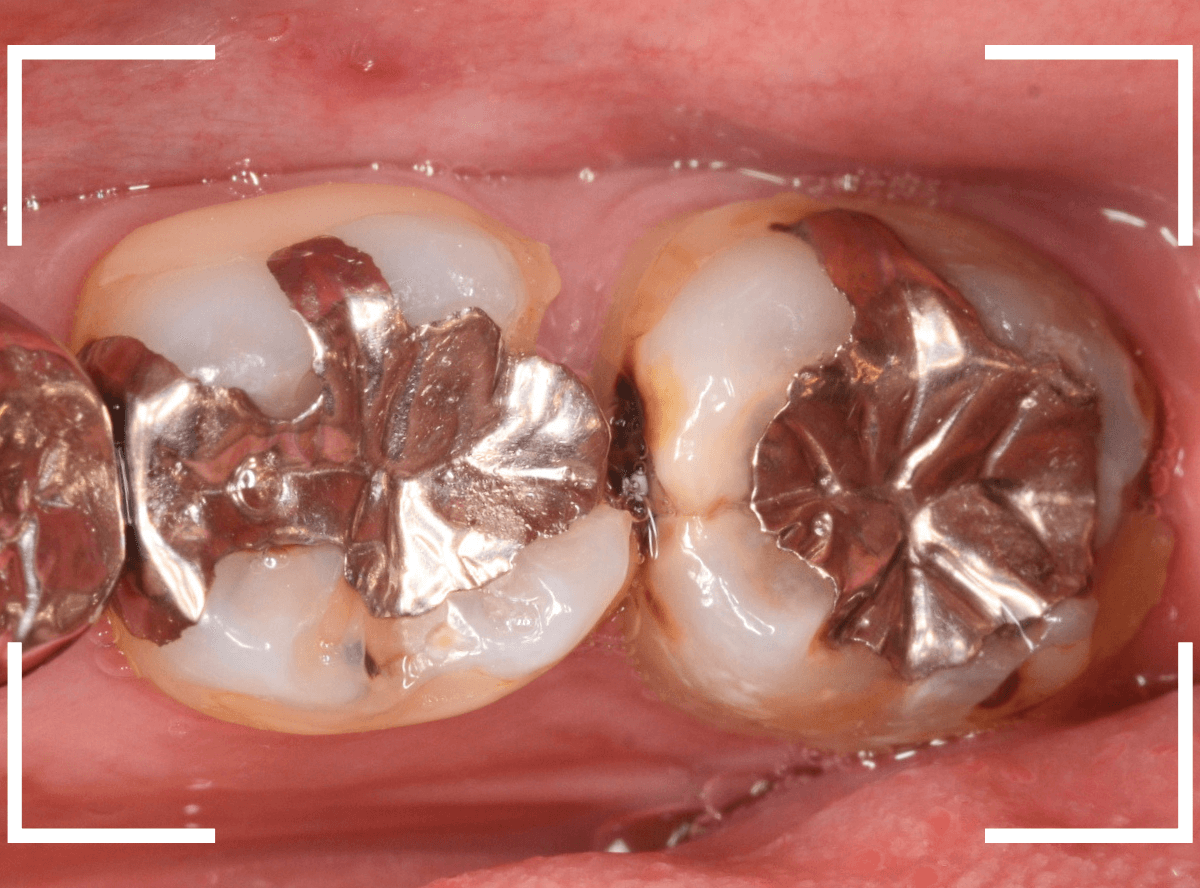

Case.10 劣化したメタルインレーの下の深い虫歯

レントゲンで大きな虫歯が見つかった方です。

古いメタル・インレーの中がぼやっと黒く透けて見えて「アヤシイ!」と思い、レントゲン写真で確認します。

他の歯の治療希望で来院された患者さんで、レントゲンで大きな虫歯が見つかった方です。

以前に虫歯を削って、レジンをつめる治療がしてあります。

表面を見る限り、特に問題はなさそうです。

メタル・インレーを外して確認します。

思った以上に虫歯は広そうです。

外したメタル・インレーの内側は真っ黒です。

慎重に全ての虫歯を除去したところです。

丸部は、神経の入り口が少し見えている状態で、かなり際どい虫歯でした。

しばらく経過観察後、特に症状もみられませんでしたので、問題なしと判断して最終修復に移ります。

最終的にメタル・インレーをsetしたところです。

メタル・インレーの欠点の一つに他の材料に比べてしみやすい、というのがあります。

今回は、歯の神経のすぐそばまでの際どい虫歯でしたので、メタル・インレーはしみやすいので、慎重に経過観察の必要があります。